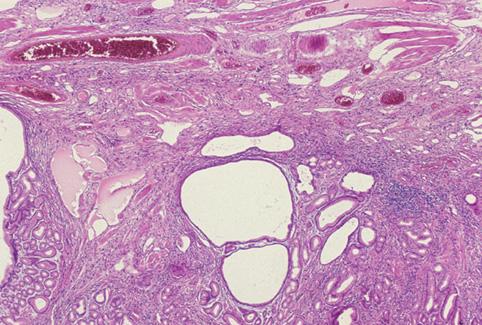

Hamartomatous inverted polyp(heterotopic gastric gland polyp)과 inflammatory fibroid polyp의 성상을 동반한 유경성의 위 융기성 병변

위(부위)/전정

30~34